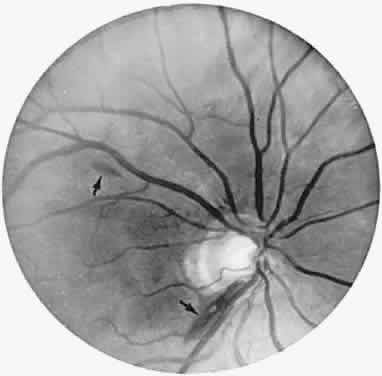

The ganglion cell layer of the retina is a principal site of abnormal accumulation of anomalous storage products, such that ophthalmoscopic changes are observable either in the form of retinal “graying” or the well-known cherry-red spot. The ganglion cell layer densely surrounds the thin fovea, which transmits the normal red color of underlying choroid (Fig. 4). The storage disorders with cherry-red spot or macular graying are listed in Table 2.27

Fig. 4. “Cherry-red spot” of advanced Tay-Sachs disease (gangliosidosis). Note the central foveal window surrounded by a ring of densely opaque retinal ganglion cell layer; also, optic atrophy.